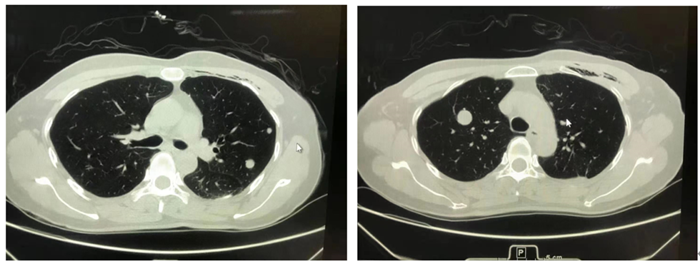

据黎女士自述,她是去年体检时发现双侧肺部多发结节,体检医生建议进一步专科诊断。于是,黎女士来到我院呼吸与危重症医学科接受检查,通过PET-CT影像学检查考虑肺部良性病变可能性大。呼吸与危重症医学科医生建议黎女士动态观察复查,其结果也均显示双肺多发结节基本保持稳定。今年5月,黎女士再次来我院复查CT,发现部分结节稍增大(图1、2),我院肺部多学科诊疗团队(MDT)就黎女士的病情展开讨论,最终考虑良性病变,建议胸腔镜下手术活检病理检查明确结节性质。于是,黎女士入院胸外科、心脏大血管外科,完善术前检查后,于6月4日由胸外科、心脏大血管外科主任袁跃西完成在胸腔镜下左肺多个结节微创切除手术。手术标本(图3)送病理科进行快速冰冻病理切片会诊,30分钟后被诊断为良性肿瘤。结合患者10年前有“子宫肌瘤”手术病史,病理科副主任蒋莎莉、主任医师王志敢等多名专家集体讨论,多头显微镜下反复阅片,辅以详细的免疫组化标记验证,发现肿瘤组织特异性表达平滑肌肿瘤标志物和雌孕激素受体,最终确诊为肺部良性转移性平滑肌瘤(PBML)(图4、5)。

图1                                                                        图2

图1、2胸部CT图片分别显示左、右侧肺部(黑色)类圆形灰白结节,好似“夜空中的一轮圆月”

王志敢主任医师介绍,肺部良性转移性平滑肌瘤(PBML)主要发生于育龄期有子宫肌瘤或子宫切除病史的女性。患者无特异性临床表现, CT表现为双侧肺部(黑色背景)多发大小不一类圆形结节(白色),具有一定特征,可以形象地称为“夜空中的一轮圆月”。偶尔可为肺部单发结节。罕见情况下可发生于心血管、骨骼肌、淋巴结等部位。该肿瘤因生长缓慢,不会严重影响肺功能,可带瘤生存数十年,因此极易漏诊。自首次报道该肿瘤至2020年6月,有人在WJCC(World Journalof Clinical Cases)杂志上统计全球仅有100例。近10年来,91短视频